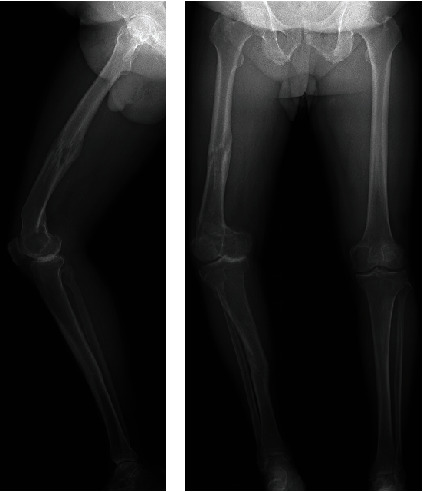

Background: Knee osteoarthritis (OA) with extra-articular deformity (EAD) is a rare condition for which achieving accurate alignment with total knee arthroplasty (TKA) is difficult. Extra-articular corrective osteotomy may be necessary for severe deformities. Case Presentation: A 76-year-old man underwent TKA for knee OA with EAD due to malunion after fractures of the femur and tibia. The femoral varus and the tibial valgus/recurvatum deformities were mild and corrected by intra-articular osteotomy using navigation (i.e., navigation-assisted standard TKA). However, the femoral antecurvatum deformity was severe, and we performed extra-articular corrective osteotomy simultaneously with TKA. Navigation was used not only for TKA but also for extra-articular corrective osteotomies. The osteotomy site was fixed with a cemented stem and metaphyseal sleeve. The postoperative hip-knee-ankle angle was 1° varus, the femoral implant was implanted at 0.5° varus/0.5° flexion, and the tibial implant was implanted at 0.5° varus/0° posterior slope. Two years after surgery, improvements were obtained in the range of motion from 15°-95° to 0°-110°, the Knee Society Score from 39 to 92 points, and the functional score from 35 to 100 points. Conclusions: One-stage TKA with extra-articular corrective osteotomy achieved good clinical results due to accurate alignment using navigation and firm fixation of the osteotomy site using cemented-stem and metaphyseal sleeve without any fixation devices.

背景:膝关节骨性关节炎(OA)伴有关节外畸形(EAD)是一种罕见病,很难通过全膝关节置换术(TKA)实现精确对位。严重畸形可能需要进行关节外矫正截骨术。病例介绍:一名 76 岁的男性因股骨和胫骨骨折后发生骨不连而导致膝关节 OA,并伴有 EAD,接受了全膝关节置换术。股骨内翻和胫骨内翻/后凸畸形较轻,并通过导航下的关节内截骨手术(即导航辅助标准 TKA)得到了矫正。但股骨前凸畸形严重,我们在进行TKA的同时进行了关节外矫正截骨术。导航不仅用于TKA,也用于关节外矫正截骨术。截骨部位用骨水泥柄和骺套固定。术后髋关节-膝关节-踝关节角度为1°屈曲,股骨假体植入角度为0.5°屈曲/0.5°弯曲,胫骨假体植入角度为0.5°屈曲/0°后倾。术后两年,患者的活动范围从15°-95°增加到0°-110°,膝关节社会评分从39分增加到92分,功能评分从35分增加到100分。结论一期 TKA+关节外矫正截骨术取得了良好的临床效果,这得益于使用导航精确对位,以及使用骨水泥干和骺端套筒对截骨部位进行牢固固定,而不使用任何固定装置。